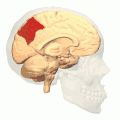

Precuneus of left cerebral hemisphere (shown in red). -

Medial surface of left cerebral hemisphere. (Precuneus visible at top left.) -

Medial surface of left cerebral hemisphere. (Precuneus colored in red.)